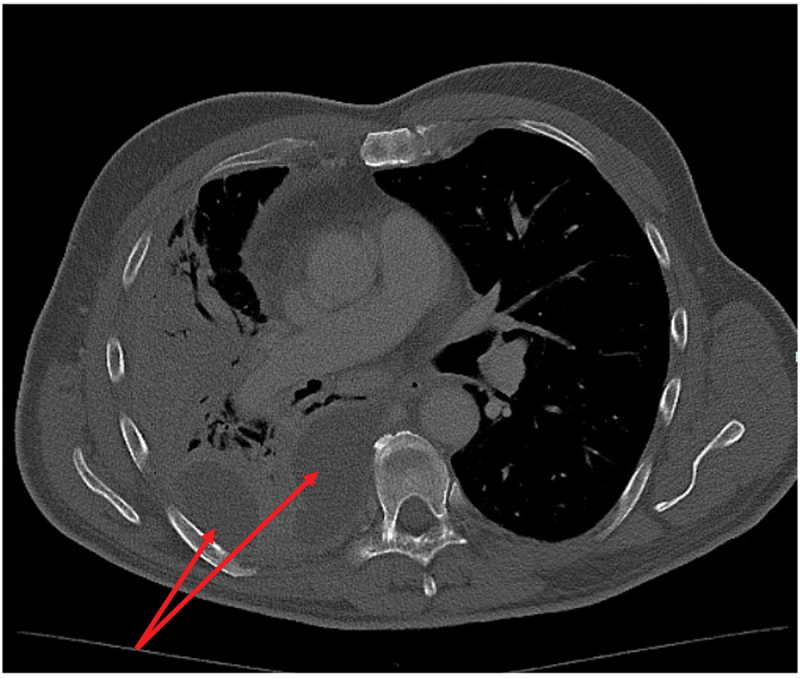

Serotype 3 pneumococcal infection can cause severe invasive disease, even in immunocompetent adults, and is potentially preventable by vaccination. Invasive pneumococcal disease caused by serotype 3 is currently the most frequent serotype found in adults in Denmark. In this report, we present a 62-year-old immunocompetent man diagnosed with a severe pleural empyema caused by serotype 3, requiring a long course of antibiotics. The patient experienced clinical improvement, and follow-up imaging showed near-complete resolution of lung infiltrates. We also review the epidemiology of serotype 3 invasive pneumococcal disease in adults in Denmark and discuss the challenges related to serotype 3 and effective vaccines.